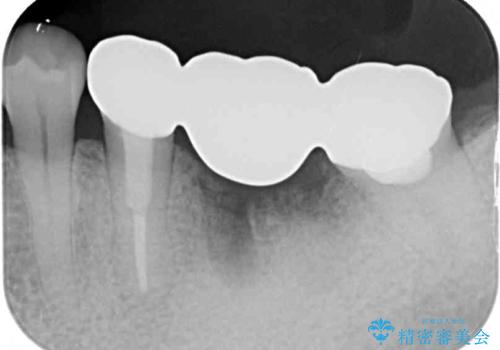

インプラントあるいはブリッジによる補綴治療が考えられましたが、前後の歯が大きな銀歯であったため、オールセラミックブリッジにより3本の歯を審美的に仕上げることとしました。

奥歯の治療をしている間に前歯の治療をどのように勧めるのか検討していただき、最終的には4歯を一度に治療し、審美的に仕上げることとしました。

ブリッジの支台歯は2本とも神経を取り除いている歯であるため、咬合力の強い方ですと、支台歯も歯根破折をするリスクがあります。

今回はそれほど咬合力が強いとは思われなかったため、ブリッジによる補綴治療を行いましたが、念のため、就寝時にはナイトガードとしてマウスピースを装着するようお願いしました。